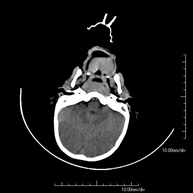

- Neuroradiology

- Skull CT

Radiological test that provides high definition anatomical images of the skull (brain stem, cerebellum, cerebrum, cranial calotte, etc.) using CT (Computed Tomography) equipment. Indicated for: trauma, headache, memory disorders, sudden loss of strength in a limb or half of the body.